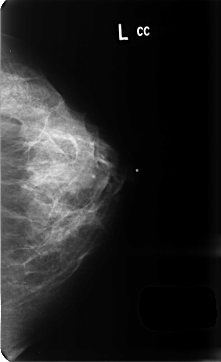

B_3436_1.LEFT_CC

LEFT_CC LINES 4704 PIXELS_PER_LINE 2872 BITS_PER_PIXEL 12 RESOLUTION 50 NON_OVERLAY